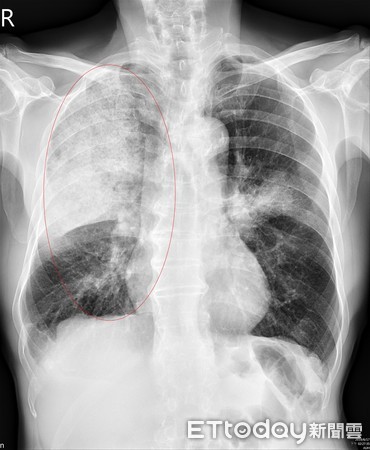

▲男子胸悶赴醫檢查,發現感染「克雷伯氏肺炎桿菌」。(圖/記者嚴云岑攝)

亞洲大學附屬醫院胸腔內科主任黃建文表示,患者就診前只覺胸口疼痛,並無發燒、咳嗽等不適症狀,還以為只是清洗魚缸時,胸口壓迫玻璃邊緣引起,沒想到胸部X光呈現大片肺炎,經電腦斷層檢查發現,為肺炎引起肋膜嚴重積膿,當下立即轉入加護病房,並會診胸腔外科醫師手術治療。經細菌培養證實為「克雷伯氏肺炎桿菌」造成,由於膿瘍範圍日益擴大,若不積極處理,恐因呼吸困難甚至敗血症,引發致命危機。